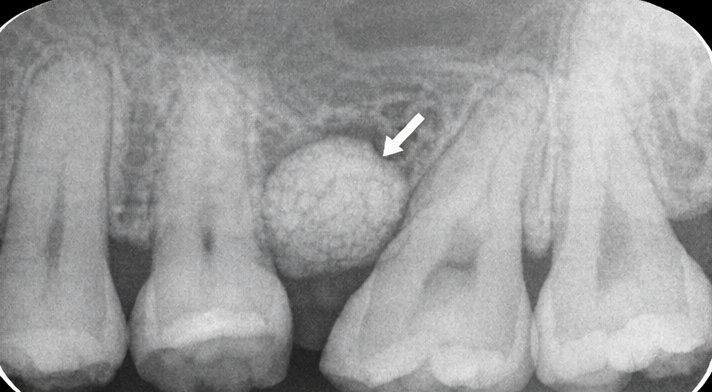

A standard intraoral periapical (IOPA) radiograph revealed a well-circumscribed radiopaque mass on the buccal aspect of the right maxillary premolar region, continuous with the underlying alveolar bone. There was no evidence of bone destruction, root resorption, periapical pathology, or periodontal bone loss.